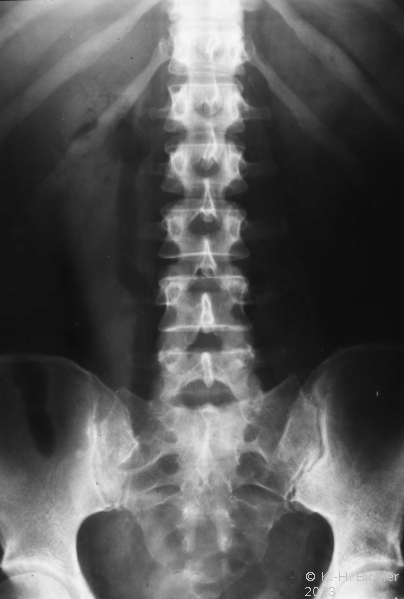

- Röntgenleeraufnahme: Luftansammlung in den ableitenden Harnwegen rechts

- Abbildung: